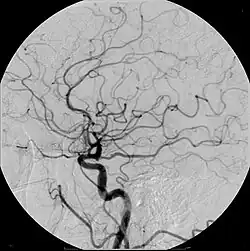

Meio de contraste, em diagnósticos por imagem, são substâncias administradas ao paciente com a finalidade de facilitar a distinção de estruturas anatômicas em seu estado normal ou patológico.

A depender da técnica de obtenção de imagens podem ser utilizadas diferentes substâncias. Mesmo a água pode ser considerada um meio de contraste quando, por exemplo, é utilizada para distender o estômago e duodeno na tomografia computadorizada (nessa ocasião considerada um contraste negativo). Meios de contraste podem ser administrados pelo trato gastrointestinal (via oral ou retal), via intravenosa, via intra-arterial, pelo trato genitourinário (ex.: vagina, útero ou uretra), ou ainda, durante procedimentos cirúrgicos, quando se deseja estudar estruturas profundas como a via biliar (colangiografia).

Quando administrado pela via intravenosa, é capaz de facilitar a identificação dos vasos sanguíneos, além de detectar alterações estruturais ou dinâmicas de funcionamento dos órgãos estudados, que em muitos casos, não seriam detectados de outra forma. Apesar de ter o potencial de alterar a função renal, na grande maioria das vezes o contraste iodado intravenoso o faz de maneira discreta e reversível, e por esse motivo, é amplamente utilizado pelo seu benefício, permitindo o diagnóstico e tratamento de condições de maior relevância para a saúde do paciente.